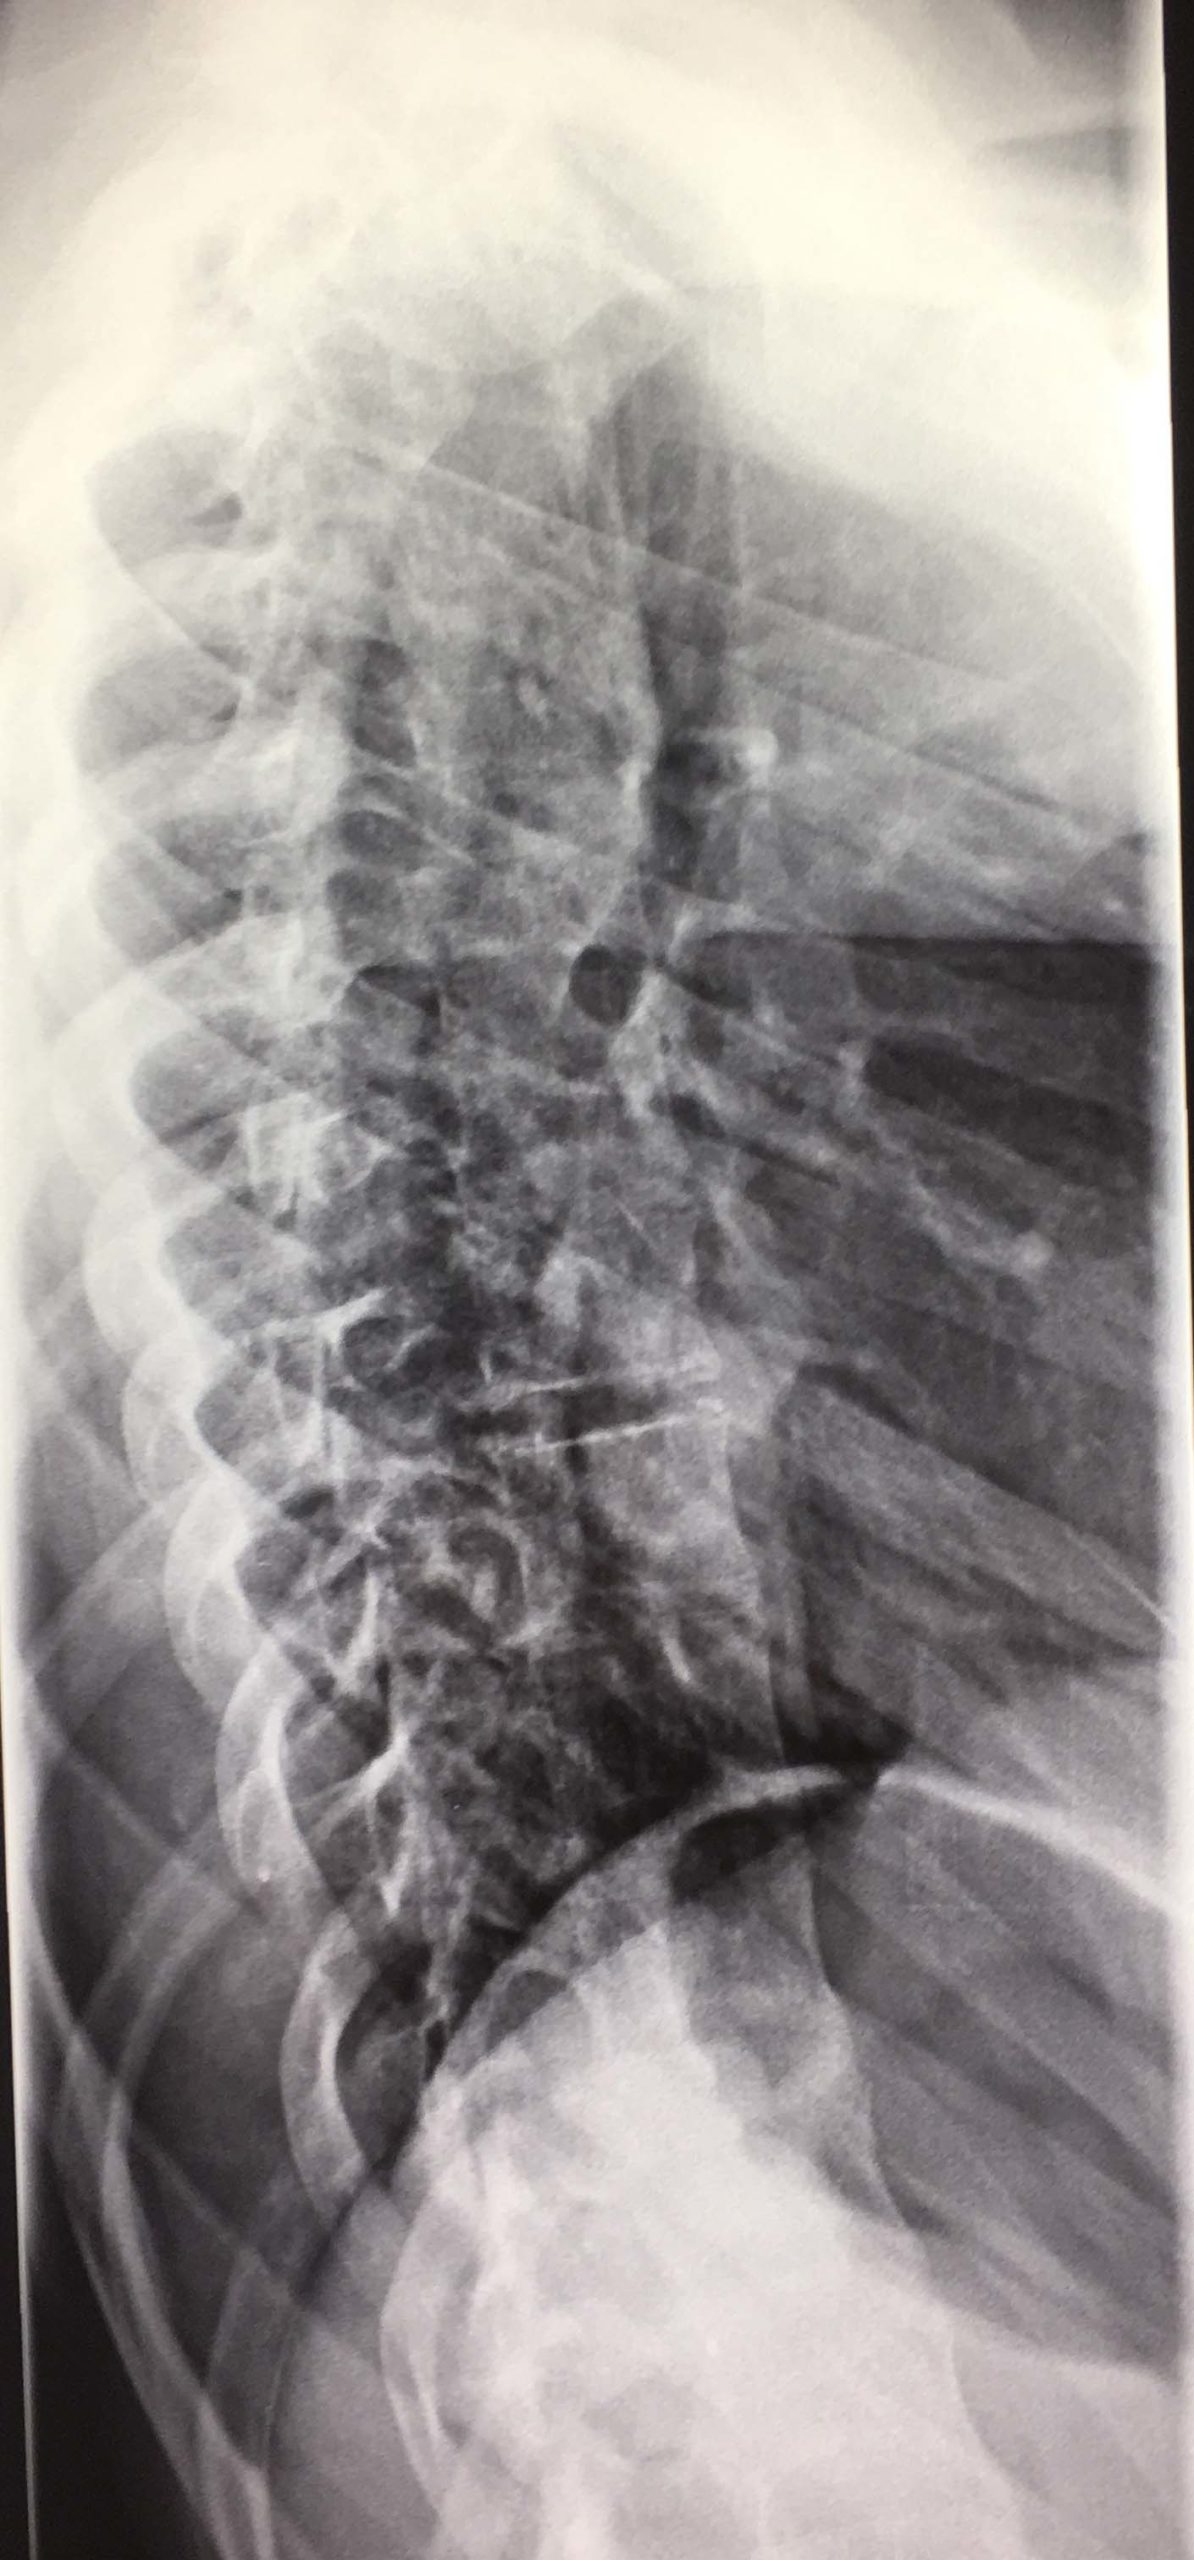

Εικόνα 3 Προσθιοπισθία ακτινογραφία Σπονδυλικής Στήλης, σε όρθια στάση

Το θωρακικό κύρτωμα είναι 56 μοίρες. Παρατηρείται μεγάλη «πτώση» των δεξιών θωρακικών πλευρών, γεγονός που αιτιολογεί το σημαντικό θωρακικό ύβο.

Η πάσχουσα, παρά το νεαρό της ηλικίας της, 14 ½ χρονών, πρακτικά είναι βιολογικά ώριμη, δεδομένου ότι έχει πραγματοποιηθεί σχεδόν πλήρως η κάλυψη της λαγονίου ακρολοφίας, από τη λαγόνιο υπόφυση (σημείο Risser 4-5).

Εικόνα 14  Προσθιοπισθία προεγχειρητική ακτινογραφία

Στο επίπεδο του κορυφαίου σπονδύλου του θωρακικού κυρτώματος (9ος) των 56 μοιρών  κατά Cobb, η πλευρά στο επίπεδο του φέρεται στο κοίλο του κυρτώματος υπό  γωνία 10 περίπου μοιρών. Ενώ στο αυτό επίπεδο δεξιά στο κυρτό μέρος του κυρτώματος, φέρεται υπό  γωνία 45 περίπου μοιρών.

Ανάλογες είναι περίπου οι πλευροσπονδυλικές γωνίες της 6ης, 7ης, 8ης, 9ης, 10ης πλευράς στο κοίλο (αριστερά) και στο κυρτό (δεξιά) του θωρακικού κυρτώματος.